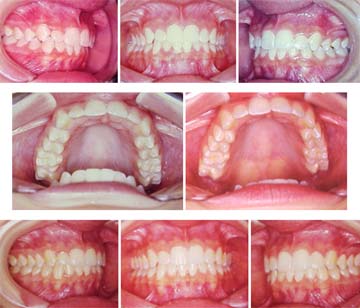

Para concluir este tema apresentaremos, como exemplo, um caso simples de mordida cruzada postural, desencadeada por respiração bucal em decorrência de uma rinite alérgica, a qual foi logo diagnosticada e convenientemente tratada. Observaremos também as prováveis implicações nas articulações temporomandibulares, estimuladas pelo uso do hiperbolóide com intuito de reprogramar o sistema estomatognático.

Com apenas seis meses de tratamento, a harmonia facial é restabelecida e o desvio postural da mandíbula deixa de influenciar a face da paciente. |